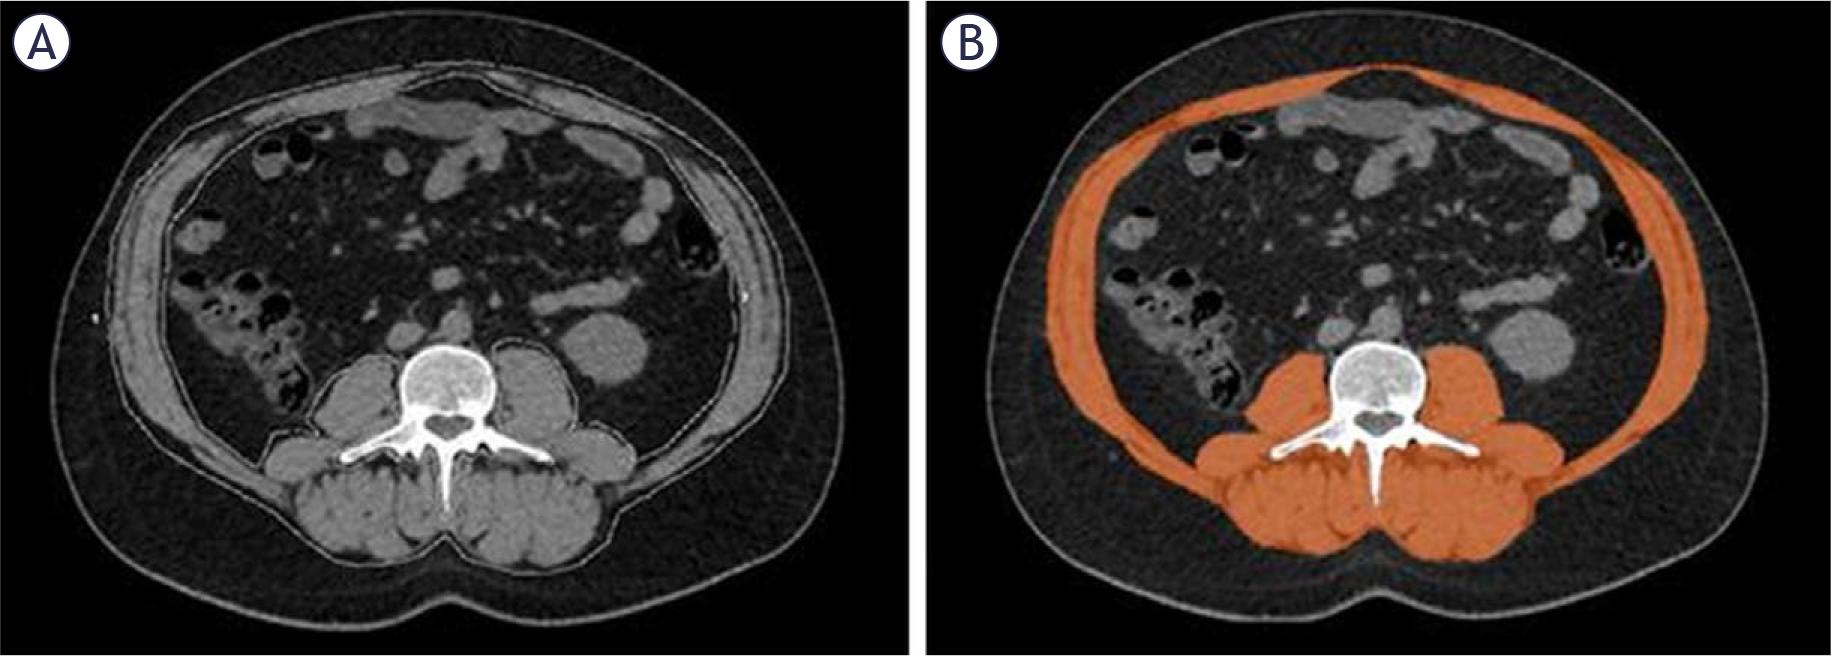

FIGURE 1.